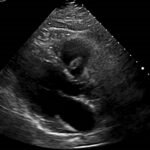

Endovascular coil embolization continues to become a more frequent modality of addressing hemorrhage and bleeding in patients. Migration refers to the coil unraveling or moving from the original embolization site. Migration of a coil is a known complication which can lead to serious consequences based on where the coil migrates. Despite increasing efforts to improve safety and technique, the risk of migration remains. We present a case of an embolization coil that migrated to the right ventricle, which was incidentally found roughly 2 months after undergoing an interventional radiology procedure for gastric variceal bleeding. The patient presented to the emergency department with dyspnea and abdominal pain. Unique images were obtained during his visit and in subsequent follow-up. As use of vascular embolization coils continues to become more commonplace, understanding the risks and complications of these procedures remains an important aspect of providing care for patients once they have left the interventional radiology suite. Coil migration should be a differential to consider in patients who present to the emergency department with signs or symptoms of arrhythmia or pulmonary embolism who have undergone a coil embolization procedure.